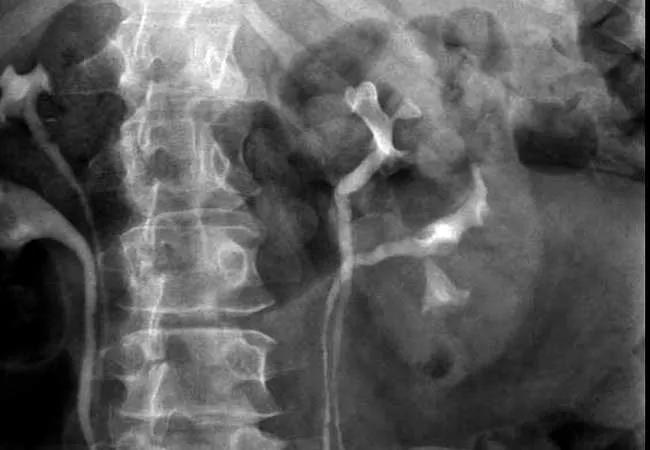

Ureteroscopy is safe and effective, no matter the ureteral anatomy, according to a Cleveland Clinic study.

Ureteral duplication is a common congenital abnormality – albeit a relatively rare phenomenon – in the urinary tract, affecting about 1 percent of the population. Patients with known duplication are cautioned prior to surgery for urinary stone disease that the ureter may be “tight” and surgery may be more difficult.

Manoj Monga, MD, FACS, FRCS, Director, Cleveland Clinic’s Center of Endourology & Stone Diseases in the Glickman Urological & Kidney Institute, and his team undertook the first study to compare urolithiasis treatment outcomes in patients with and without ureteral duplication. “Two Are No Different Than One: Ureteral Duplication Appears to Have No Effect on Ureteroscopy Outcomes” was published in the Journal of Endourology.

The team hypothesized that the complex anatomy of a duplicated ureter might decrease the efficacy and increase the risk of ureteroscopy (URS). A retrospective analysis of surgical outcomes of urolithiasis in patients with ureteral duplication revealed these patients had longer operative times, but preoperative knowledge of the abnormality did not affect operative time. The additional operating time was attributed to the surgeon gaining access to and fully examining each system as an independent renal unit.

“To our surprise, outcomes were the same whether patients had duplicated systems or not,” Dr. Monga says. “The safety and efficacy of the procedures were identical to those without duplication.”

This finding supports current practice and suggests that no additional imaging is necessary in patients with ureteral duplication. The study’s population of patients with this abnormality undergoing urinary stone treatment also represents the largest reported in the literature.

“Urologists do not need to caution patients with duplicated systems that outcomes with ureteroscopy may not be as effective,” Dr. Monga says. “Ureteroscopy is safe and effective in a patient with ureteral duplication.”